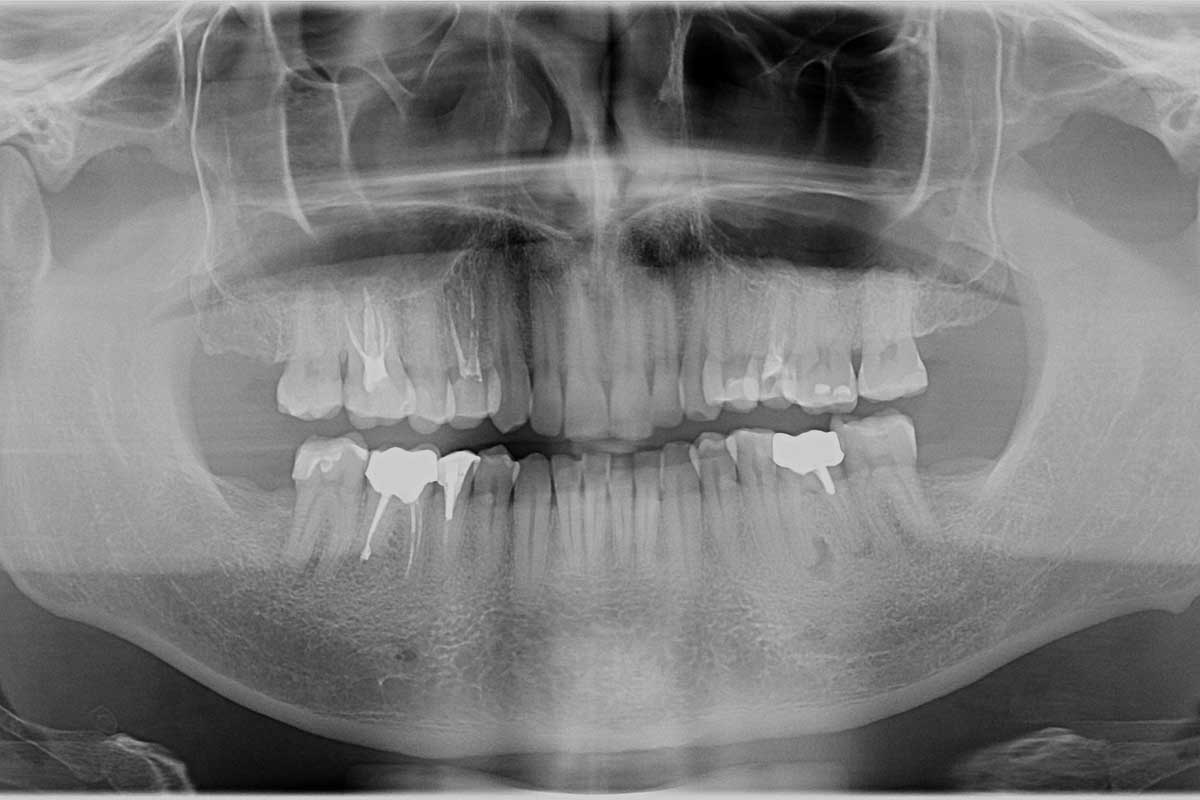

Панорамные снимки зубов до и после лечения